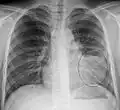

Normal AP CXR